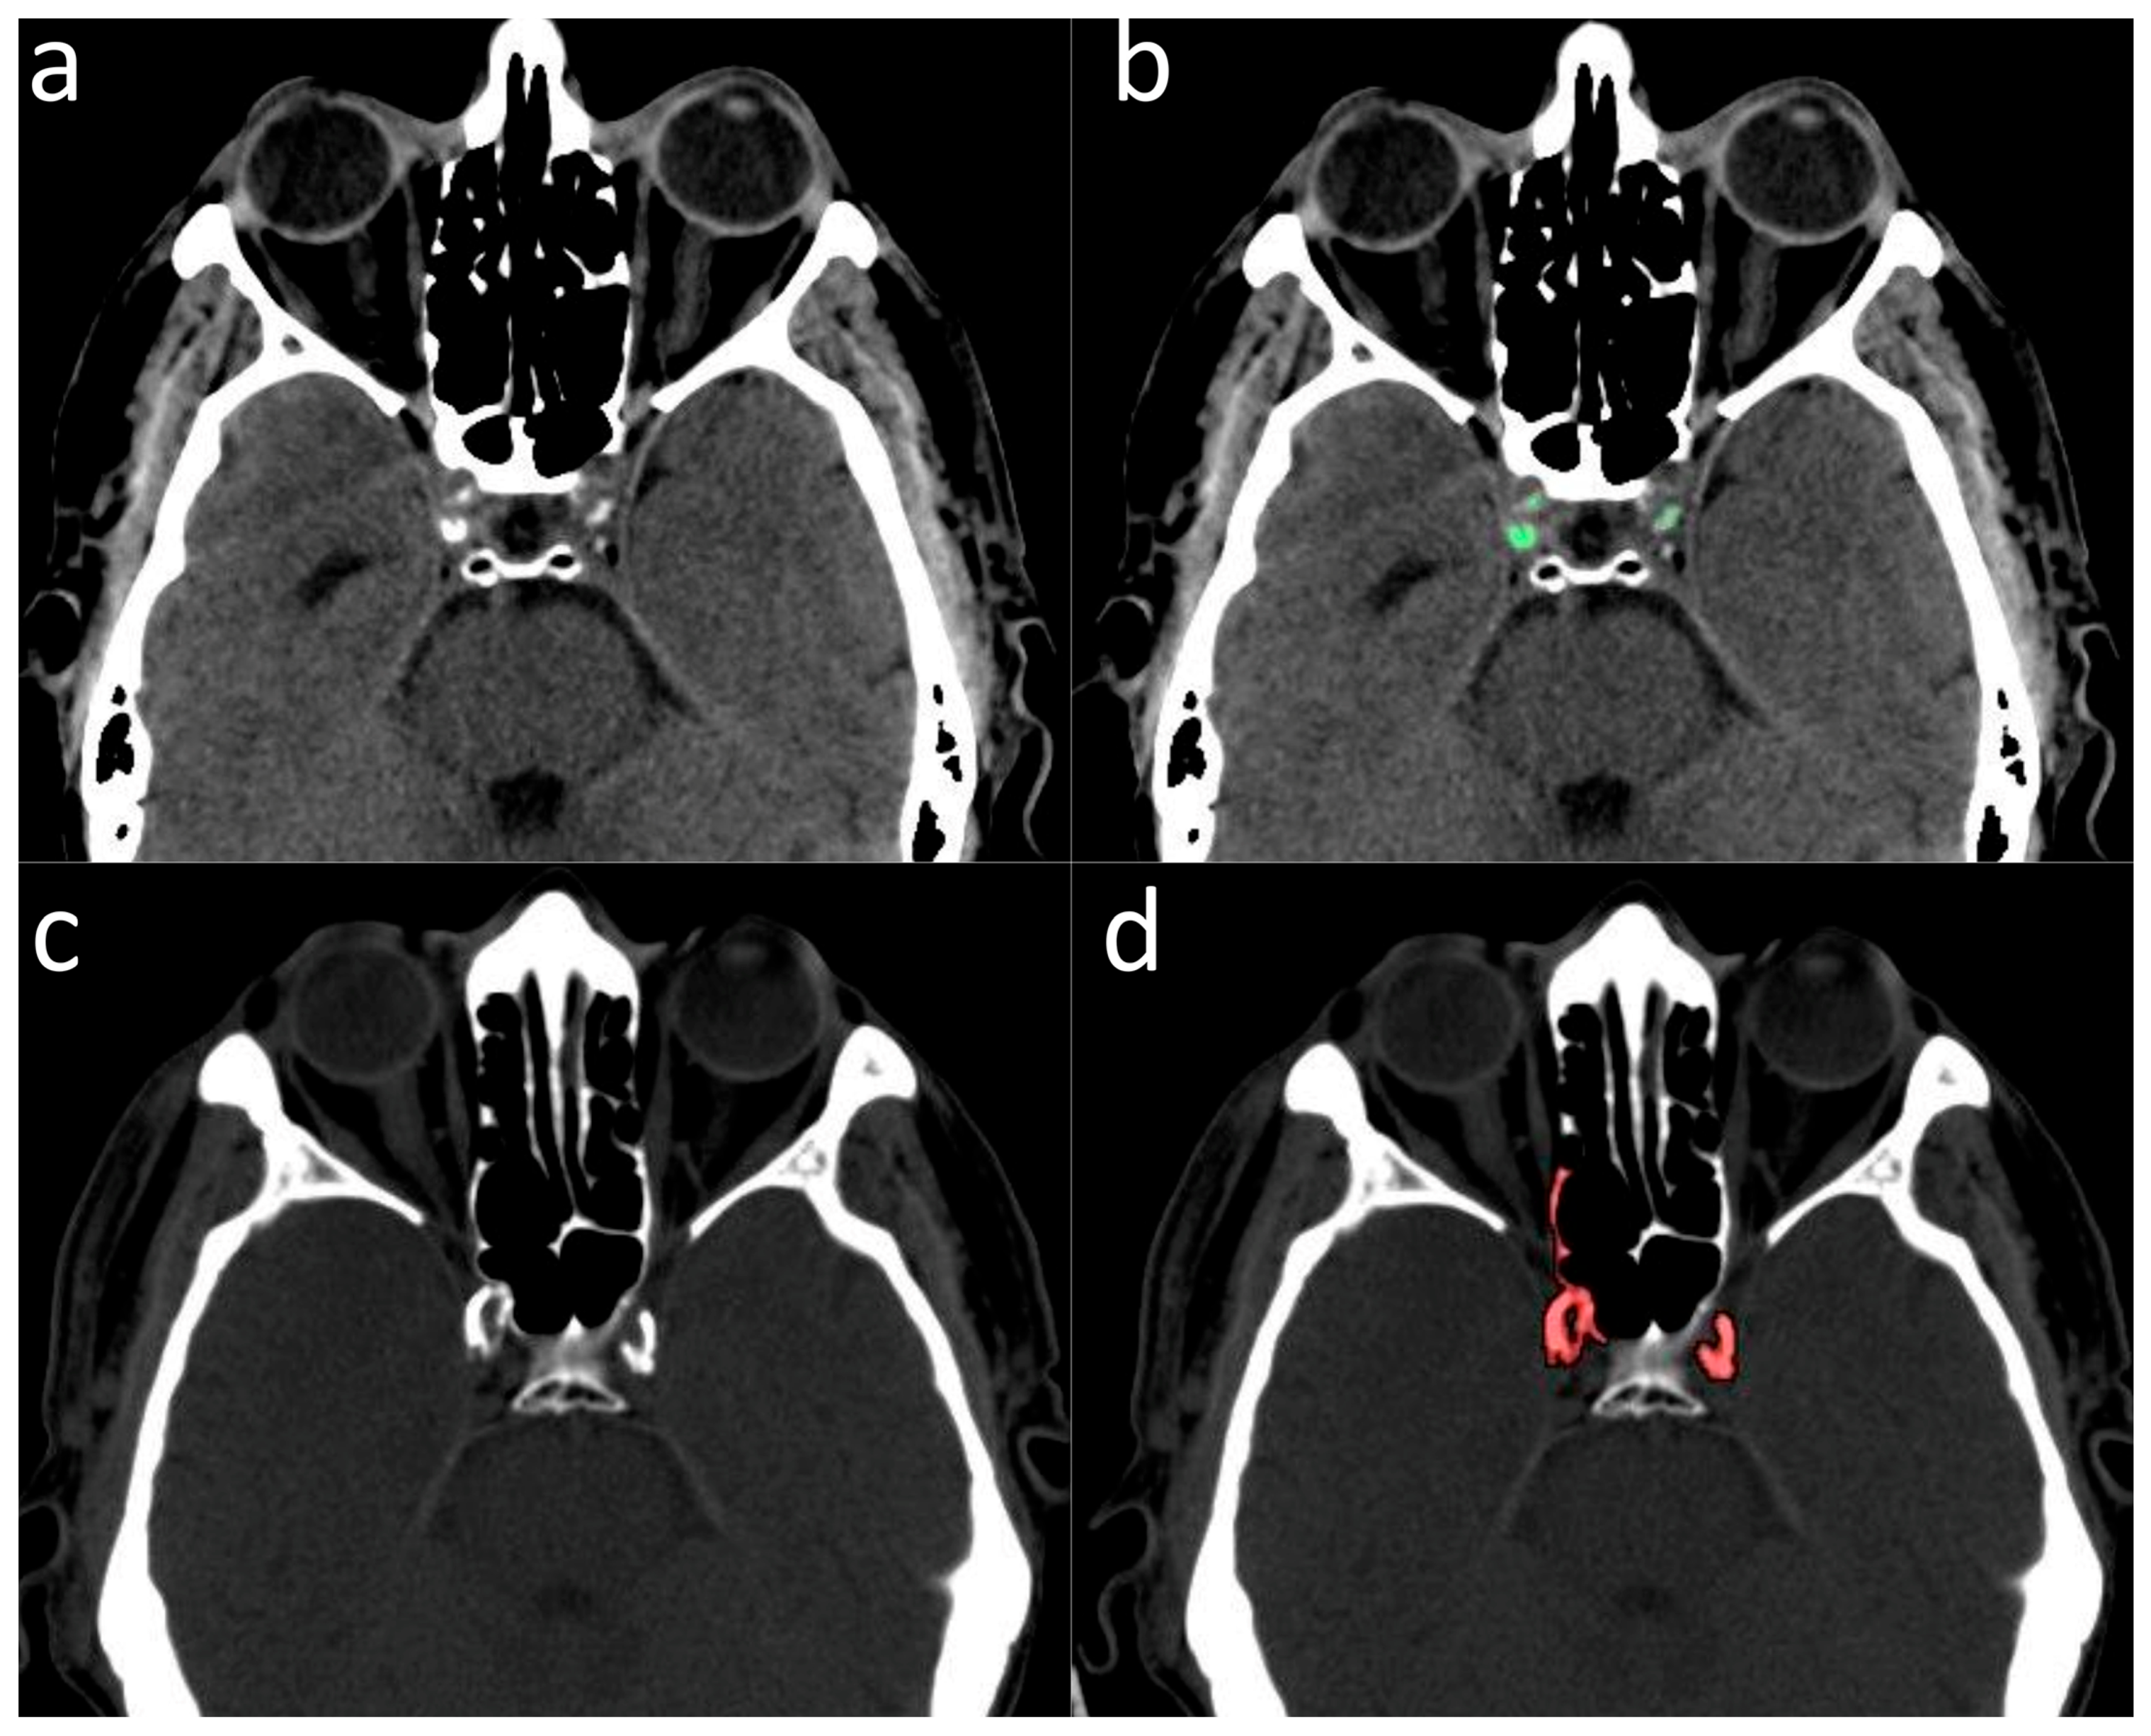

2.2. Validation of ICA Calcium Score as Surrogate Marker of CACs